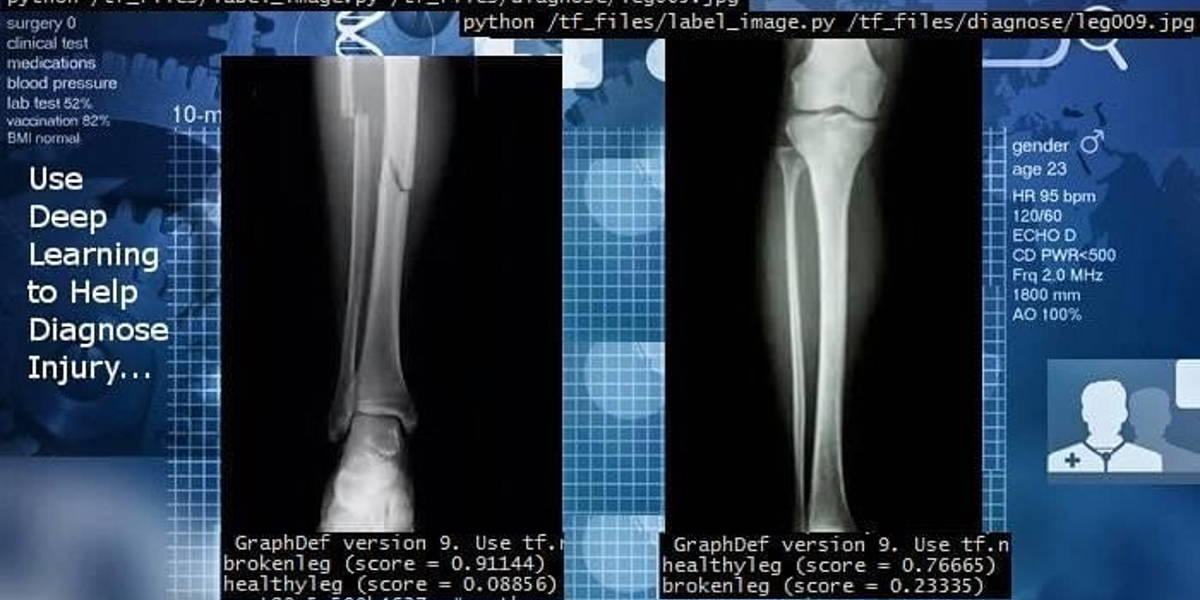

Het foutpercentage bij patroon– en beeldherkenning door kunstmatig intelligente diagnostische systemen is de laatste twee jaar gedaald tot circa 2%. Dan rijst de vraag of AI het niet beter doet dan de dokter bij het interpreteren van röntgen/ en scanbeelden of bloeduitslagen. Met nadruk op beter en niet op slimmer!

Betere c.q. nauwkeurigere diagnostiek spaart op onnodige behandelingen met risico’s, gezondheidsschade, verlies van  levens en oplopende kosten. Bij het vaststellen van kanker (o.a. long, huid, borst. bot en buik), tuberculose en bloedbeelden heeft AI-beeldherkenning in de praktijk zijn grote nut al bewezen. Waar menselijke ogen naar afwijkingen kunnen kijken kunnen neurale AI-netwerken met deep learning dat nu ook of zelfs beter. Zelfs de kleinste en potentieel mogelijke afwijkingen ontgaan het AI-algoritme met deep learning-faciliteiten niet. Het lijkt in feite al een kunstfout om deze dan ook niet in te gaan zetten. De medische wereld reageert vaak echter (te) traag op innovaties. 10-15 jaar was in het verleden normaal.